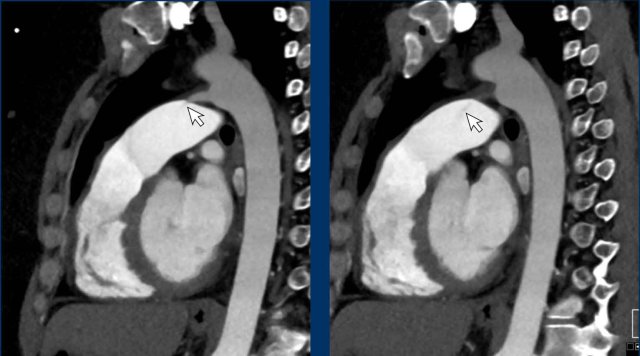

Image

Incidental cor triatriatum sinistra with delayed opacification of the right compartment of the left atrium.

This was initially misinterpreted as a thrombus.

Images

Delayed filling of the right compartment of the left atrium in a cor triatriatum sinistra.